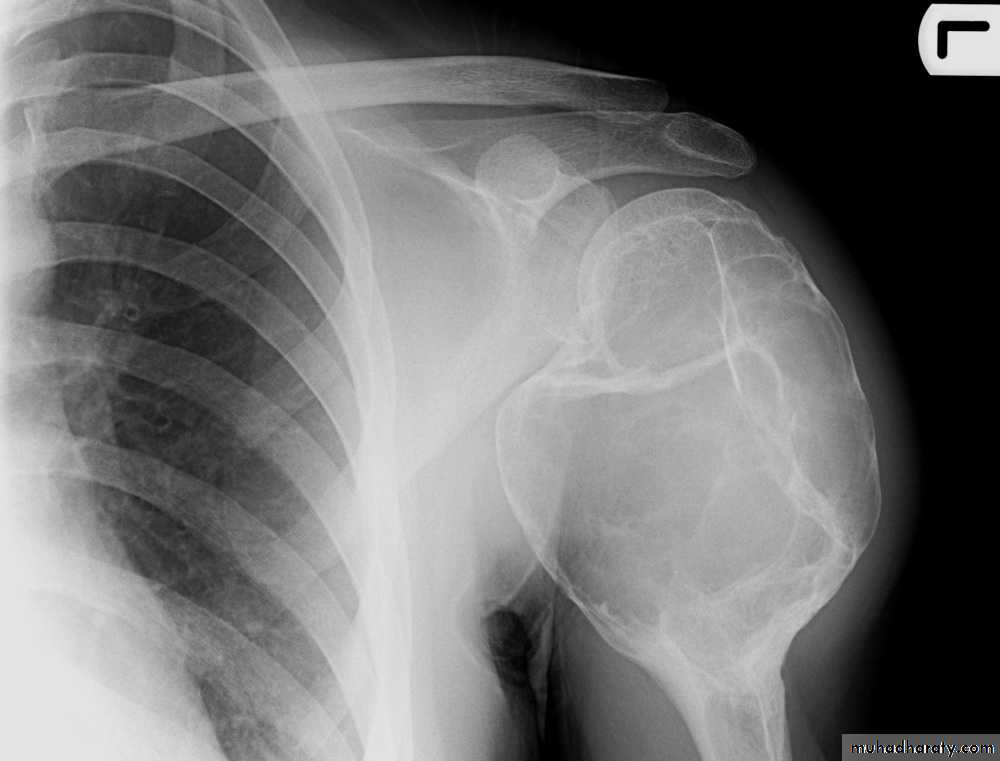

Slide 51- mention two finding?2- what is the diagnosis?